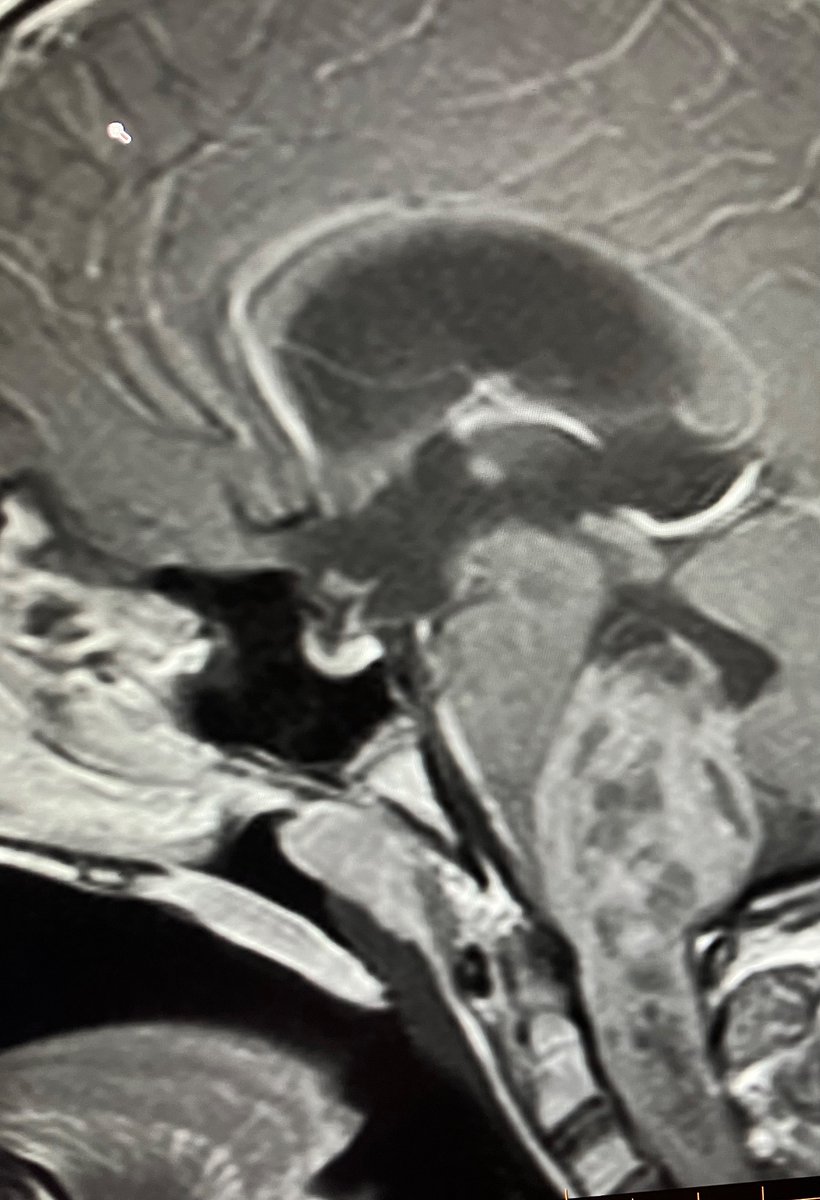

Henssen, D., Meijer, F. Cerebral aneurysm in a giant perivascular space. Neuroradiology 62, 271–272 (2020). doi.org/10.1007/s00234…

Tumefactive perivascular spaces containing an ICA aneurysm.

#radres #FOAMed #neurotwitter #Neurology #Neurosurgery